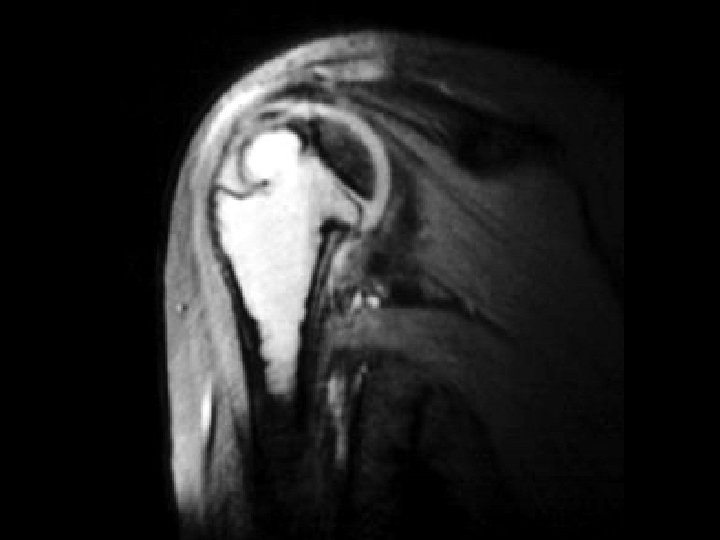

Scapular metastasis • Findings: – Soft tissue mass of the right shoulder with destruction of the adjacent scapula • ddx: – Soft tissue sarcoma